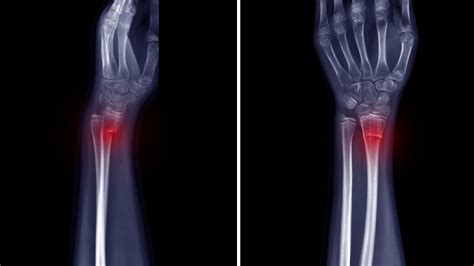

A coracoid fracture is essentially a break in the coracoid process. Now, what’s the coracoid process, you ask? Think of it as a hook-shaped bony projection that sticks out from the front of your scapula, or shoulder blade. It’s a pretty crucial part of your shoulder anatomy because several important muscles and ligaments attach to it. These include the coracobrachialis muscle , the short head of the biceps brachii muscle , and the coracoclavicular ligaments (conoid and trapezoid ligaments). These attachments are vital for stabilizing the shoulder joint and enabling a wide range of arm movements, including rotation and elevation. When the coracoid breaks, these attachments can become disrupted, leading to instability and significant pain. The coracoid itself is relatively well-protected by surrounding muscles, but it’s still susceptible to injury, especially during high-impact events. The location of the coracoid makes it particularly vulnerable to certain types of trauma. It’s not as commonly fractured as other parts of the shoulder, like the clavicle (collarbone) or the glenoid (the socket part of the shoulder joint), but when it does happen, it requires careful attention. The severity of a coracoid fracture can vary greatly, from a small chip to a complete break, and this will significantly influence the treatment approach and recovery timeline. Understanding the anatomy and the function of the coracoid process is key to appreciating the impact of a fracture. It’s the anchor point for many of the structures that allow your shoulder to move freely and powerfully. Without its integrity, the whole shoulder complex can be compromised, leading to that dreaded pain and limited mobility we often associate with shoulder injuries. So, remember that small hook-like bone? It packs a punch when it comes to shoulder function, and a fracture there means business.